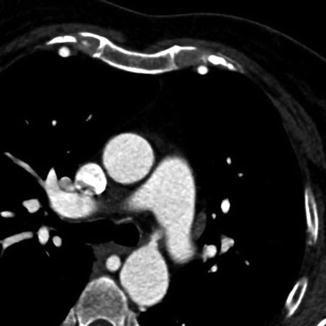

Fig. 5.5

Multiplanar reformation (MPR) technique in a patient with an aortic coarctation displaying one plane inside the original 3D image volume